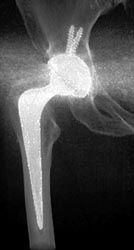

Diagnosis

Pectus Deformity